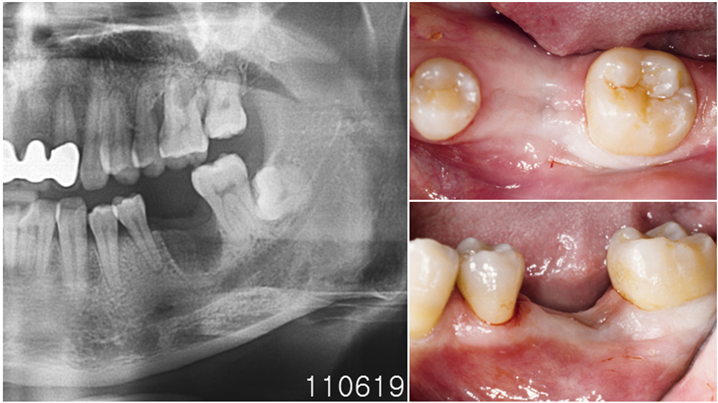

Clinical case: Bone filling into the bottom of deepest thread at 8.0mm AnyRidge fixture

- Courtesy of Dr. Kwang Bum Park -

Keywords

AnyRidge, Knifethread ,extraction socket, ,initial stability ,Allograft, ,osseointegratio ,Dr. Kwang Bum Park, , Mandibular, Single replacement, AnyRidge, Mega-oss,

Products used

Implant system-AnyRidge, Regeneration-Mega-Oss